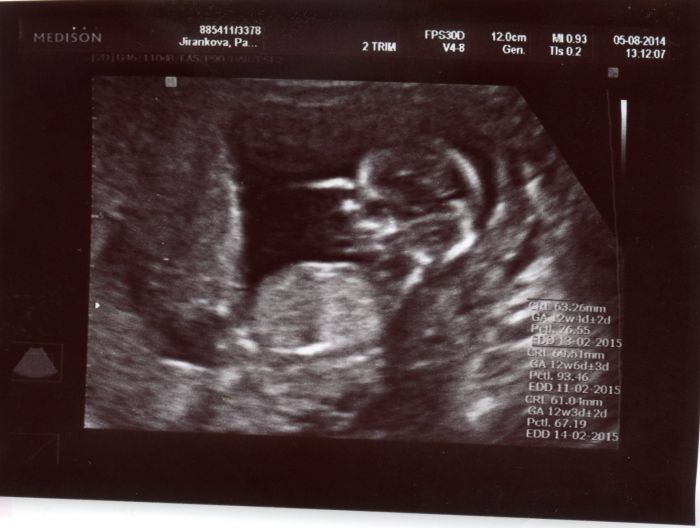

Posílám taky fotku ze včerejšího screeningu :-) dnes jsem teda 13+0, oznámila jsem to v práci, tak to většina tak čekali, někdo byl překvapenej :-)